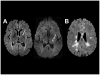

Magnetic resonance imaging (MRI) has led to the identification of widespread brain abnormalities in multiple sclerosis (MS) that extend far beyond the classic white matter lesion. These findings have generated the idea that MS should be understood as a disease of the whole brain, not just the white matter. While it is no doubt the case that many different pathways are ultimately involved in the destruction of brain tissue that occurs in MS, the implications of the accumulated evidence for understanding disease pathophysiology - and hence the overall significance of these imaging findings - are doubtful. Here, I argue that the principled use of imaging can, in fact, address questions about the genesis of these whole-brain abnormalities, rather than simply describe them.